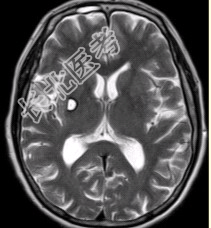

- 多项选择题2.初步拟诊为(提示MR表现如下图:既往在内蒙古生活7年。)

A、脑包虫

B、结核瘤

C、转移瘤

D、脑囊虫

E、多发性硬化

F、脑脓肿

G、腔隙性梗死